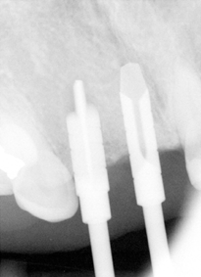

Fig.17 shows paralleling pins at 8 mm (trajectories are corrected sequentially, but not enough); Fig.18,19: reamers 4.0 mm at #7 and 3.5 mm at #8 at the depth of 11mm; Fig.20 reamers 4.0 mm at #7 (14 mm deep) and 4.5 mm at #8 (11 mm); Fig.21: Bicon implants: 4.0 x 11 mm at #7 and 4.5 x 8 mm at #8.